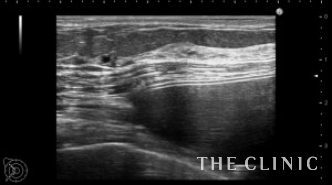

エコーでバッグの入っている部位(乳腺下か、大胸筋下か)や、カプセル拘縮の状態やバッグの破損を診断します。

この方はバッグは大胸筋下、軽度のカプセル拘縮を認めました。

バッグが挿入されている部位は、本人は覚えていないこともあり、術前のエコー診断は安全にバッグを取り出すために不可欠です。